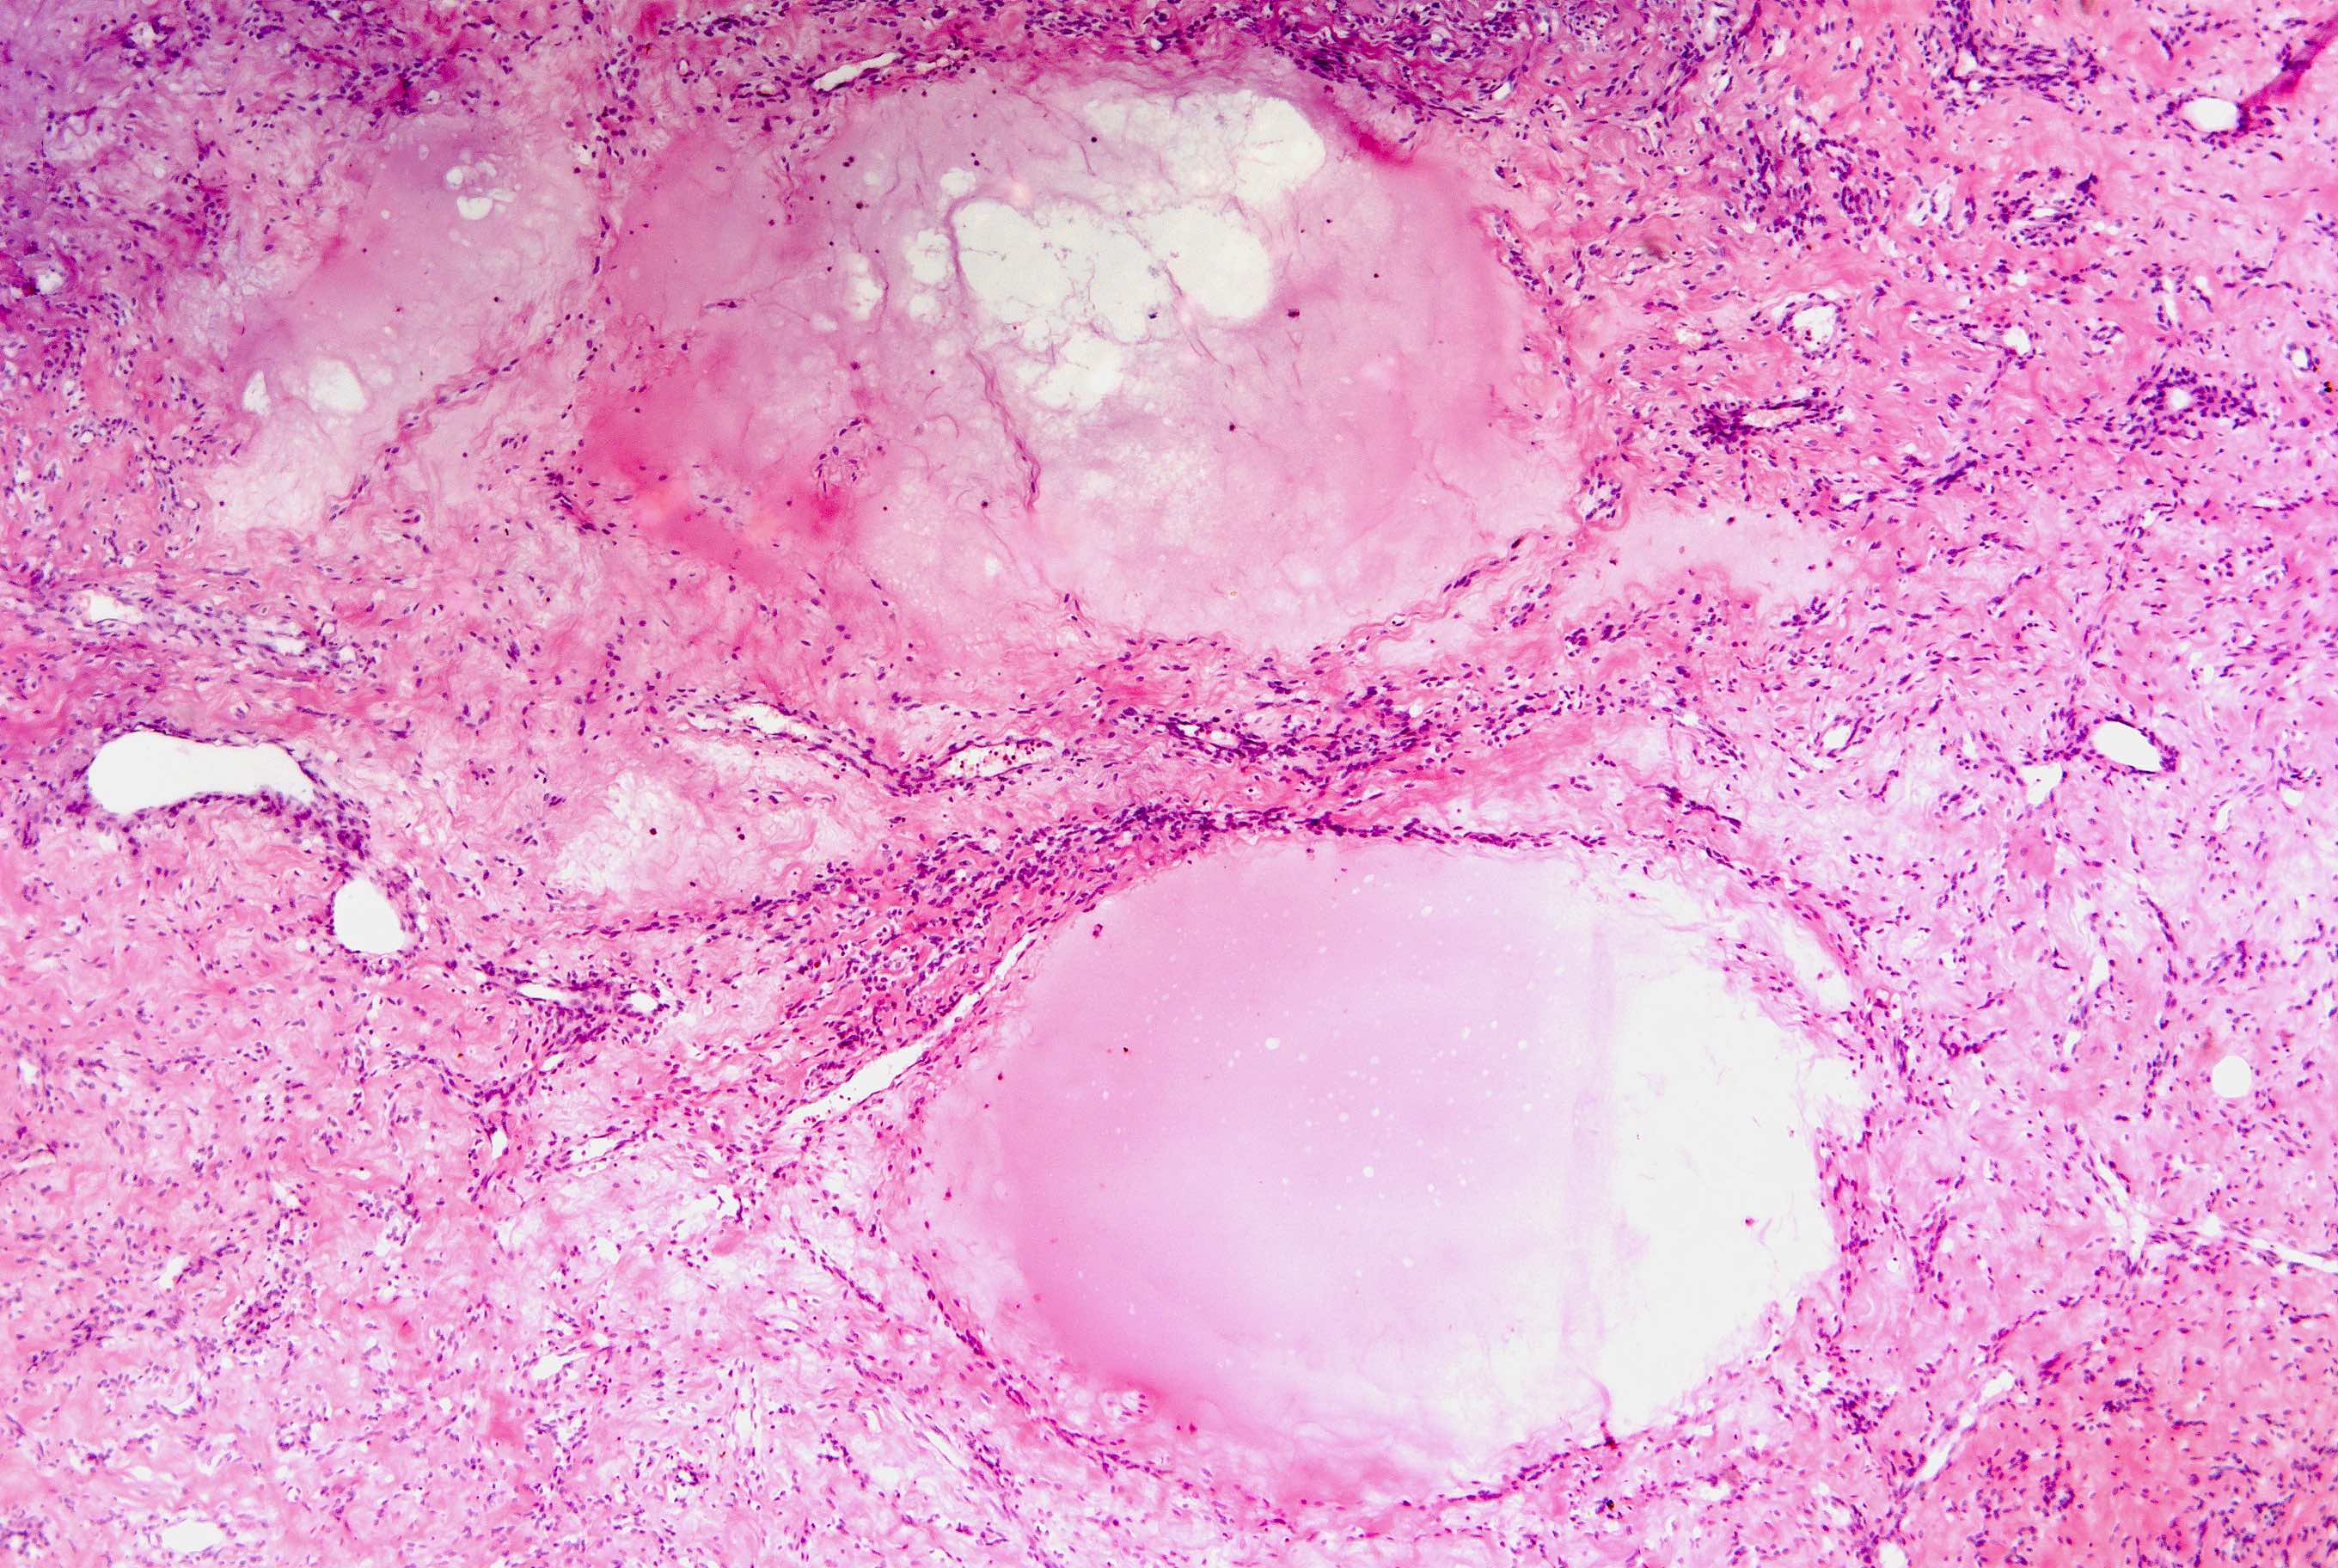

- Apoplectic:

- Central zone of hemorrhage and necrosis with increased mitotic activity in its periphery or myxoid changes (zonation phenomenon)

- Usual appearance away from the central necrosis

Microscopic (histologic) images

Contributed by Sabrina Croce, M.D., Ph.D., Kristina Doytcheva, M.D., Jennifer A. Bennett, M.D. (Case #508) and @Andrew_Fltv on Twitter